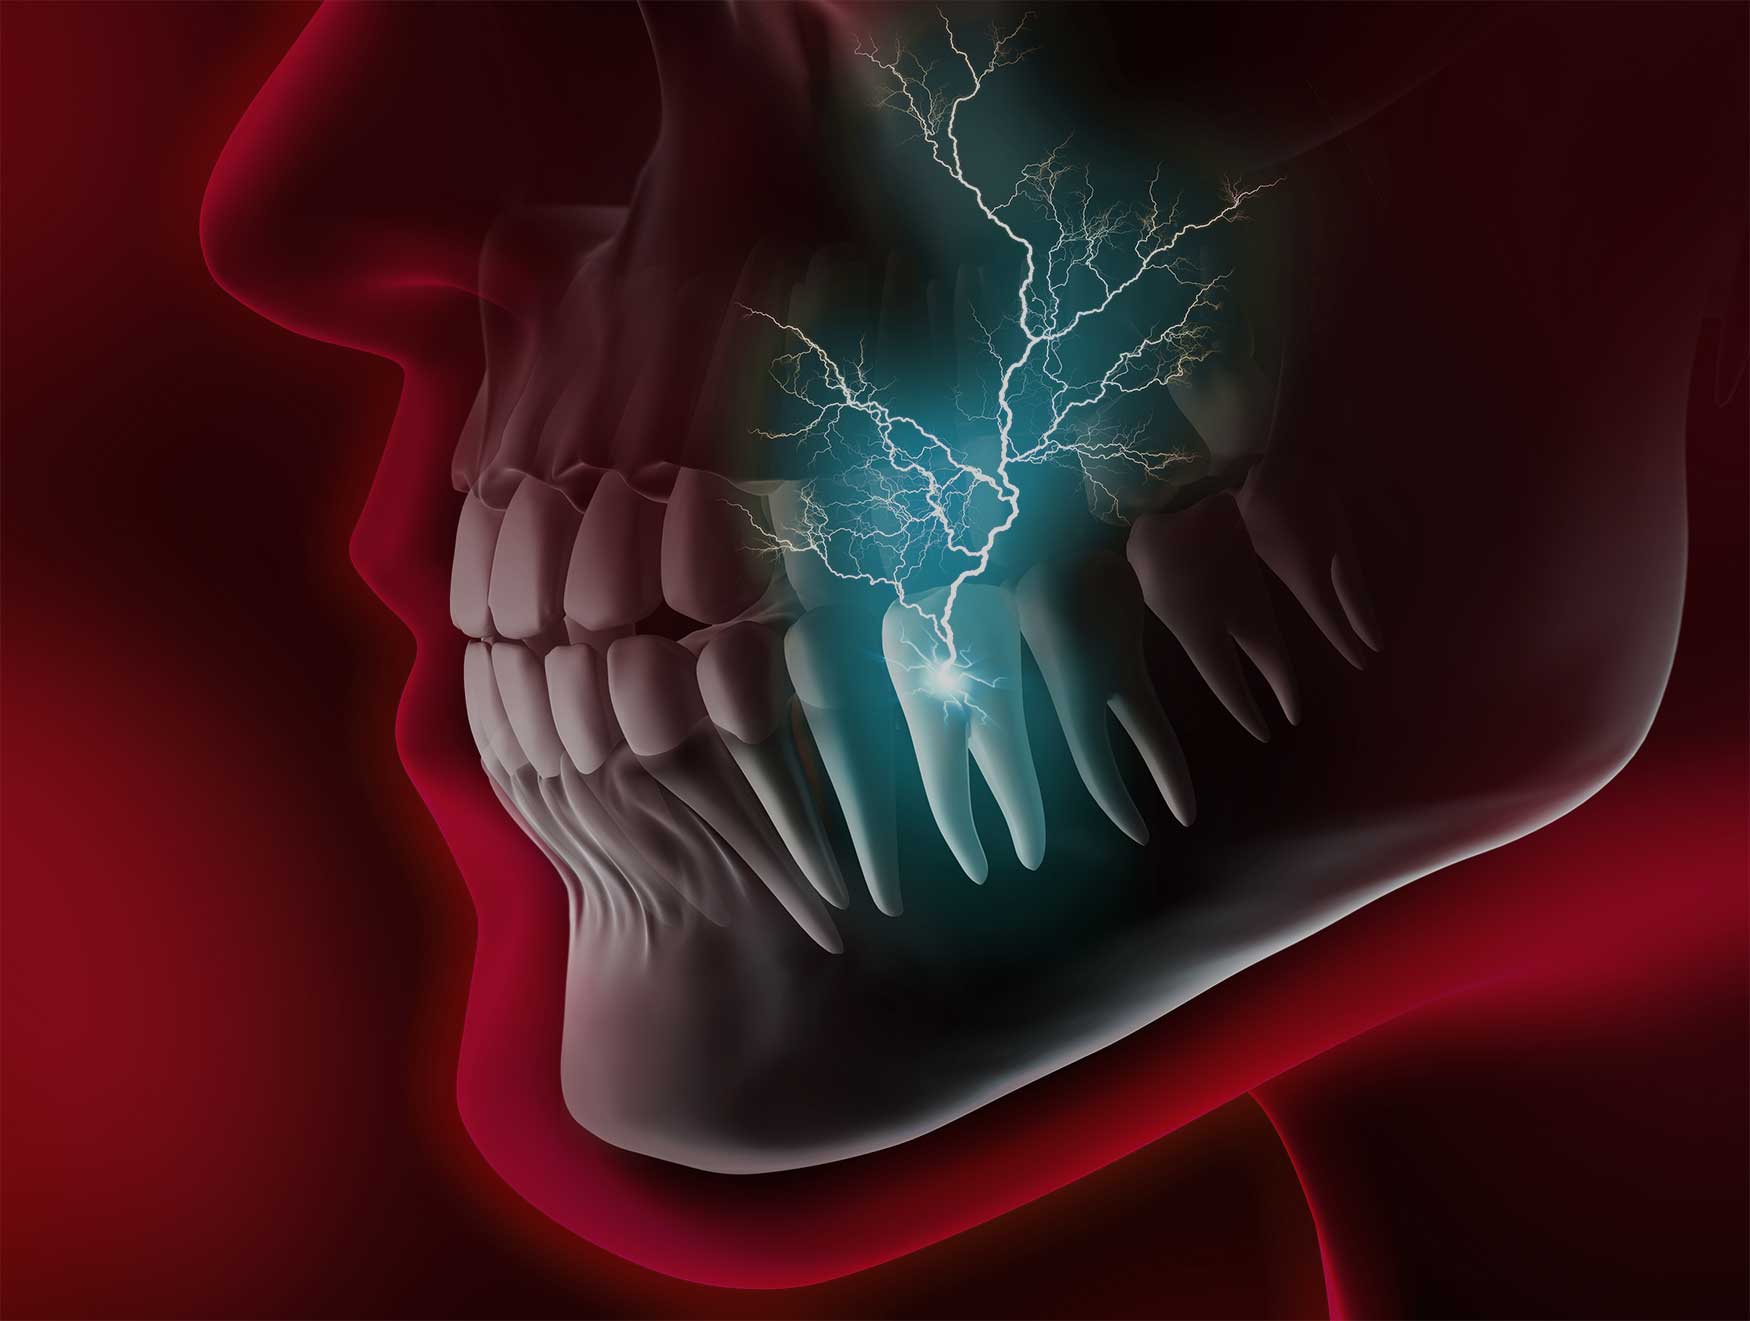

Wenn die Zähne weh tun …

Parodontose ist die Erkrankung des Zahnhalteapparates. Der Zahnhalteapparat, das sind der Kieferknochen, die bindegewebigen Haltefasern um den Zahn und die Mundflora.

Eine Parodontose hat viele Ursachen: